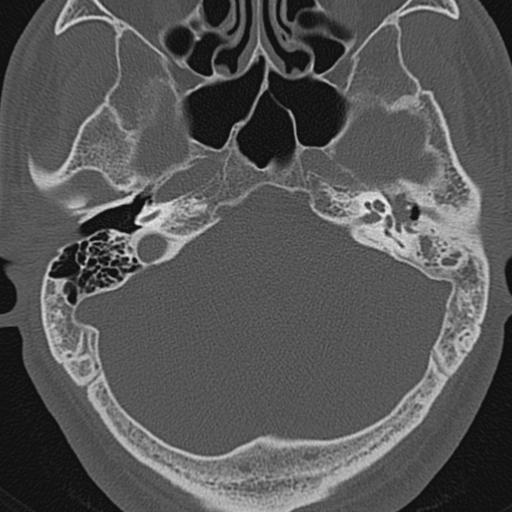

以下是引用zxl51642在2009-8-25 13:37:00的发言:[br]1、左侧慢性硬化型中耳乳突炎(中耳鼓室腔及听小骨受累),并胆脂瘤形成;2、左侧外耳道软组织密度影填塞,考虑炎性肉芽肿,建议结合临床;3、右侧颈静脉窝较左侧明显扩大,不排除颈静脉球瘤,建议mr进一步检查。

以下是引用随光逐影在2009-8-25 19:05:00的发言:[br]1)左侧慢性中耳乳突炎(肉芽肿或胆脂瘤形成),左侧外耳道炎性肉芽肿。2)右侧颈静脉球高位。